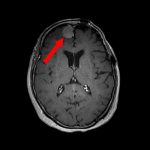

711

'25年12月

60代

良性頭蓋咽頭腫

頭蓋内腫瘍摘出術

No.’25_113 手術前1

No.’25_113 手術前2

No.’25_113 摘出 前

No.’25_113  摘出 中

No.’25_113 摘出 後